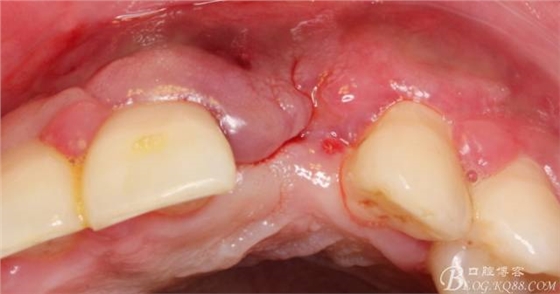

術(shù)后1個月。

術(shù)后5個月。